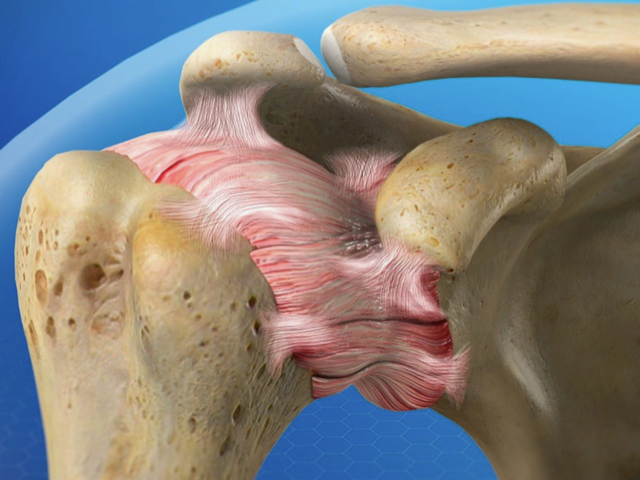

A capsulite adesiva ou ombro congelado, como também é conhecida, é uma condição em que a cápsula articular que envolve o ombro, fica inflamada, e fica mais espessa, levando a dor e limitação de movimentos.

Imagem mostrando a capsula inflamada